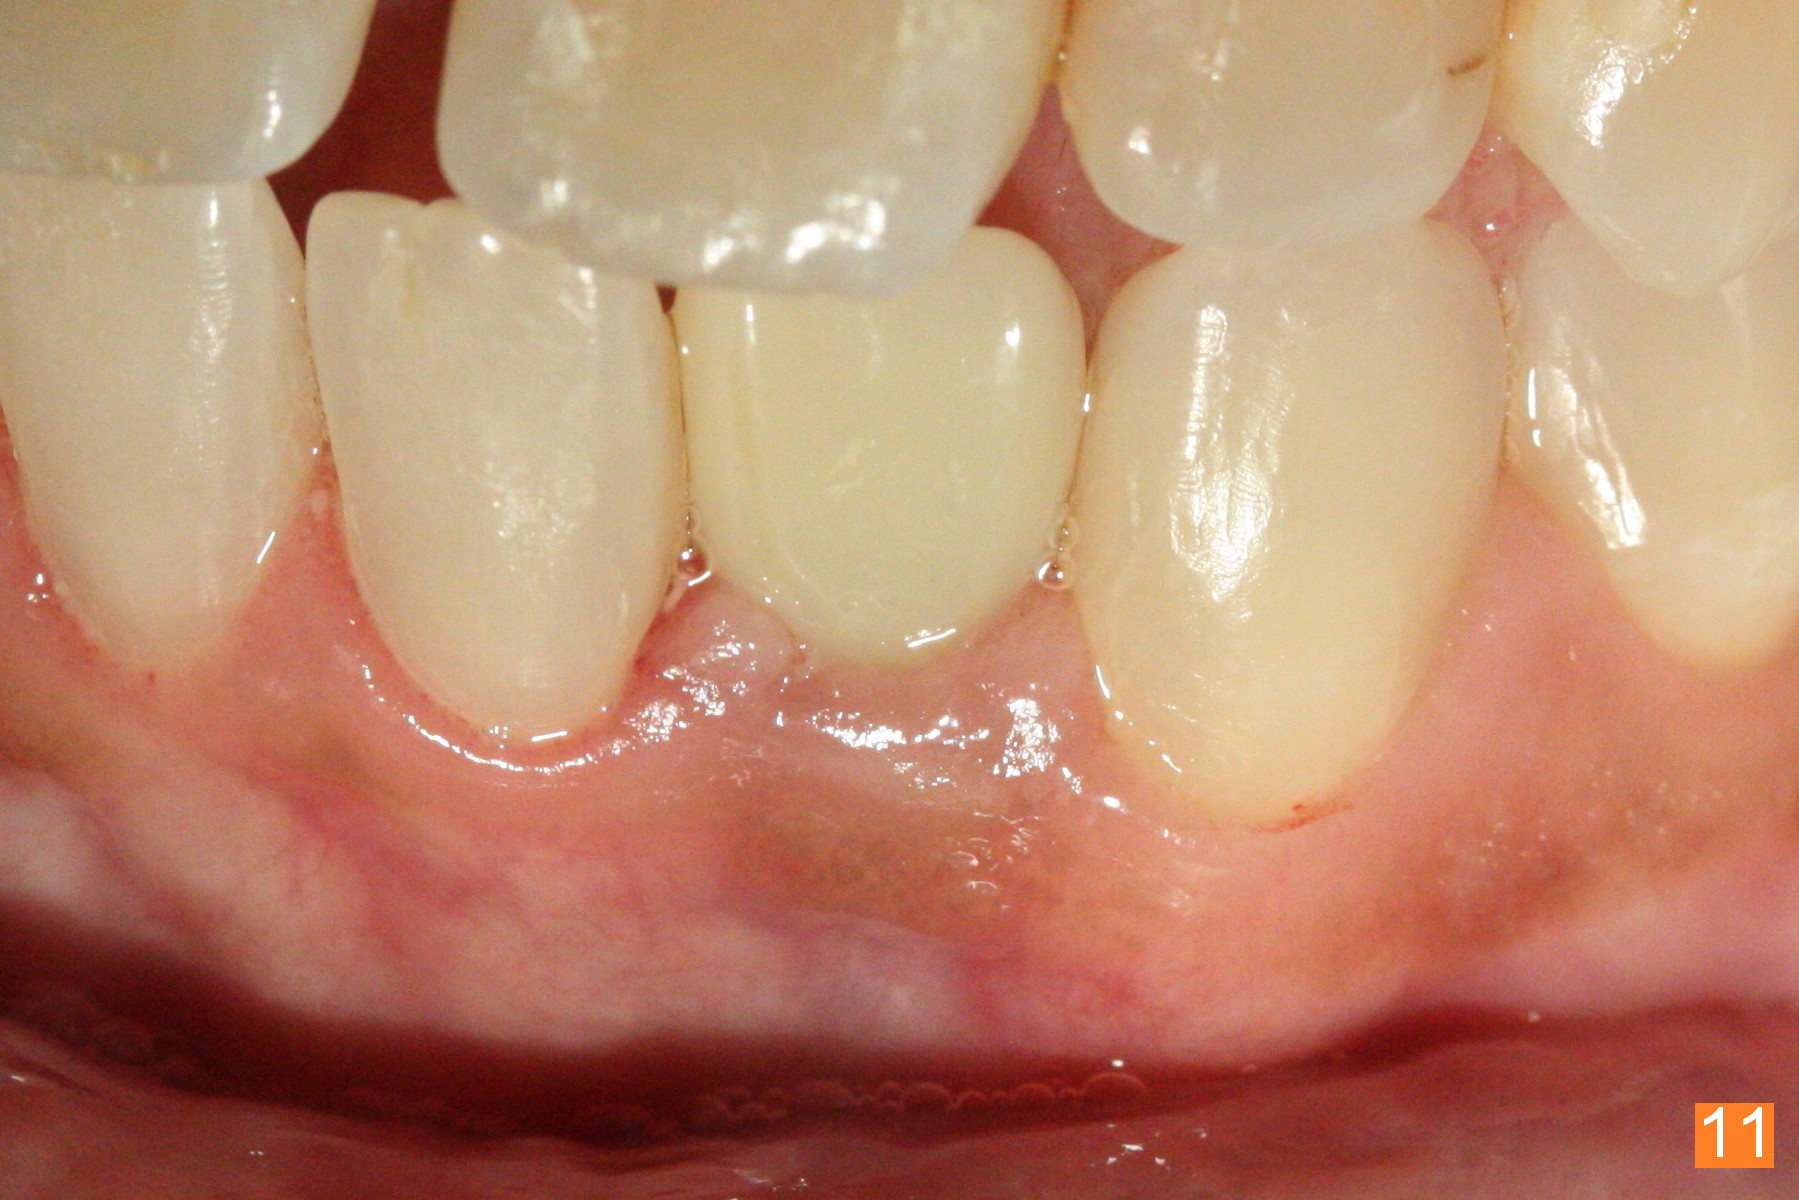

Fig.10: A2 shade guide. The patient requests A1 for the incisal edge and body and A2.5 for the cervical region. Fig.11 is taken 22 months post 2nd cementation (4 years postop). The implant crown remains normal 1 year 10 months post 2nd cementation (4 years 10 months postop, Fig.12,13).